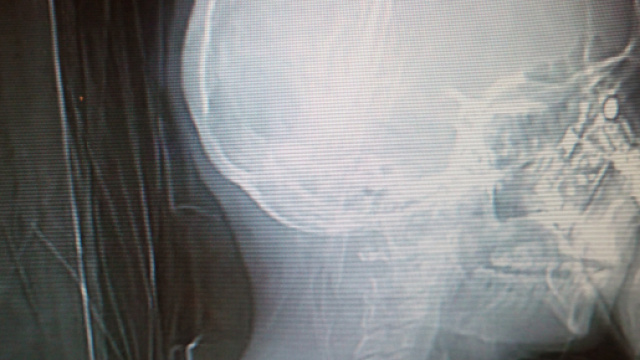

Davanti agli occhi increduli degli specialisti radiologi compare infatti la sagoma scheletrica della signora, oggetto della tac, che tranquillamente se ne sta con il suo cellulare all'orecchio candidamente intenta a rispondere ad una chiamata in corso.

La signora aveva portato con sè il suo cellulare durante la tac